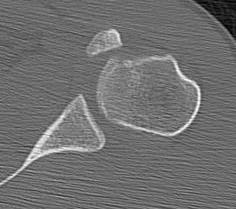

CT

Lesser tuberosity can become overgrown

Medial row anchors and lateral screws for missed lesser tuberosity avulsion in adolescent